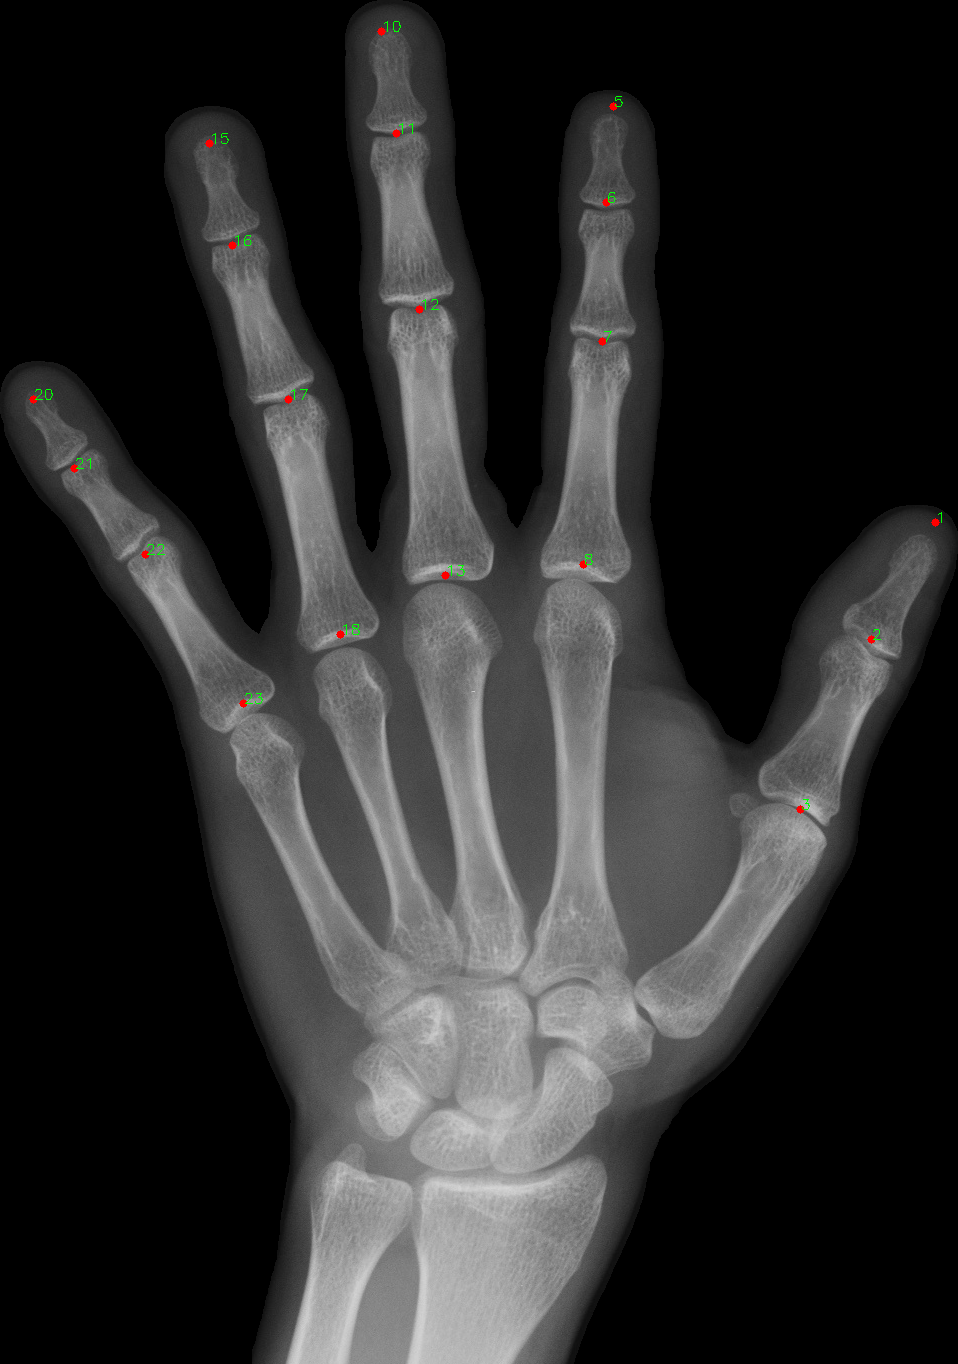

Labeling of finger landmarks in hand xrays.

Finger landmark labeling for left handed x-ray images

This project uses two algorithms (symbolic and neural) to extract finger landmarks from left hand x-rays. It's intended to be used as an auxiliary tool for forensics research at UNAM.

Note that the symbolic algorithm only approximates landmarks in four fingers (not including the metacarpophalangeal joints).